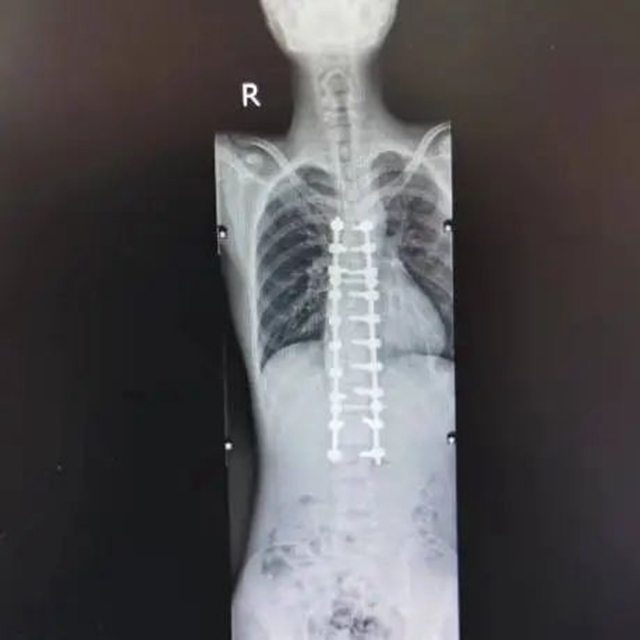

术后影像

准备就绪后,罗琳副教授、罗成副教授、罗焘医师等顺利为小黄实施了脊柱侧弯截骨矫形植骨融合内固定术。术后3天,小黄即可佩戴胸腰椎支具下床自主行走,身高也长了5厘米,差不多有180厘米,再也不弯腰驼背了,双脚也有力了。